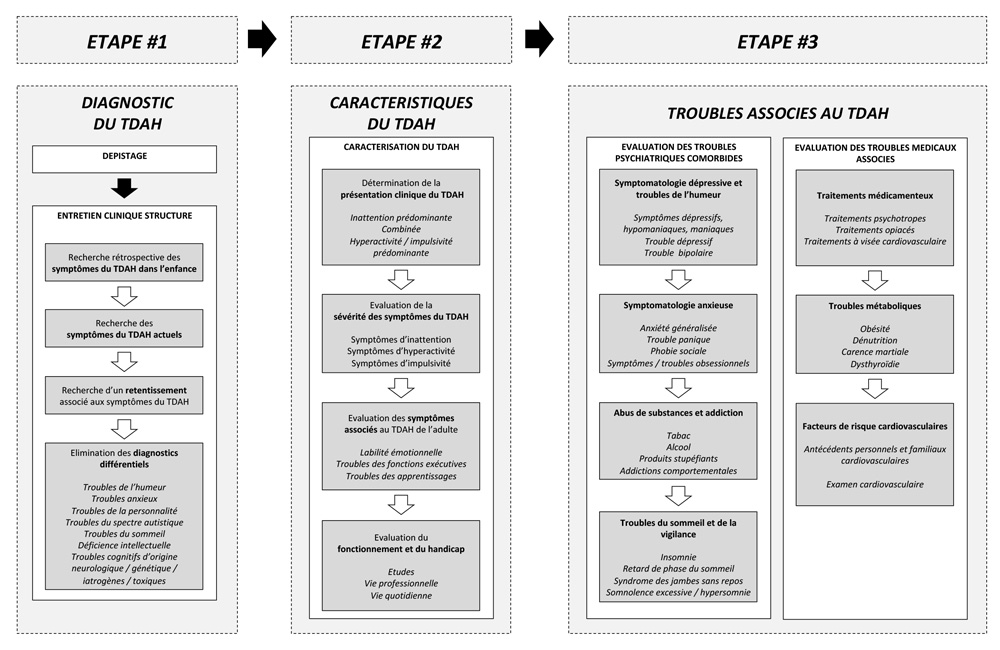

■ Le diagnostic médical sera fait dans la plupart des pays francophones sur la base de 2 à 3 entretiens avec un psychiatre ou un neurologue. Le TDAH peut être mis aussi en évidence par une IRM (images des deux cerveaux ci-dessous), même si cela n’a pas valeur de diagnostic.